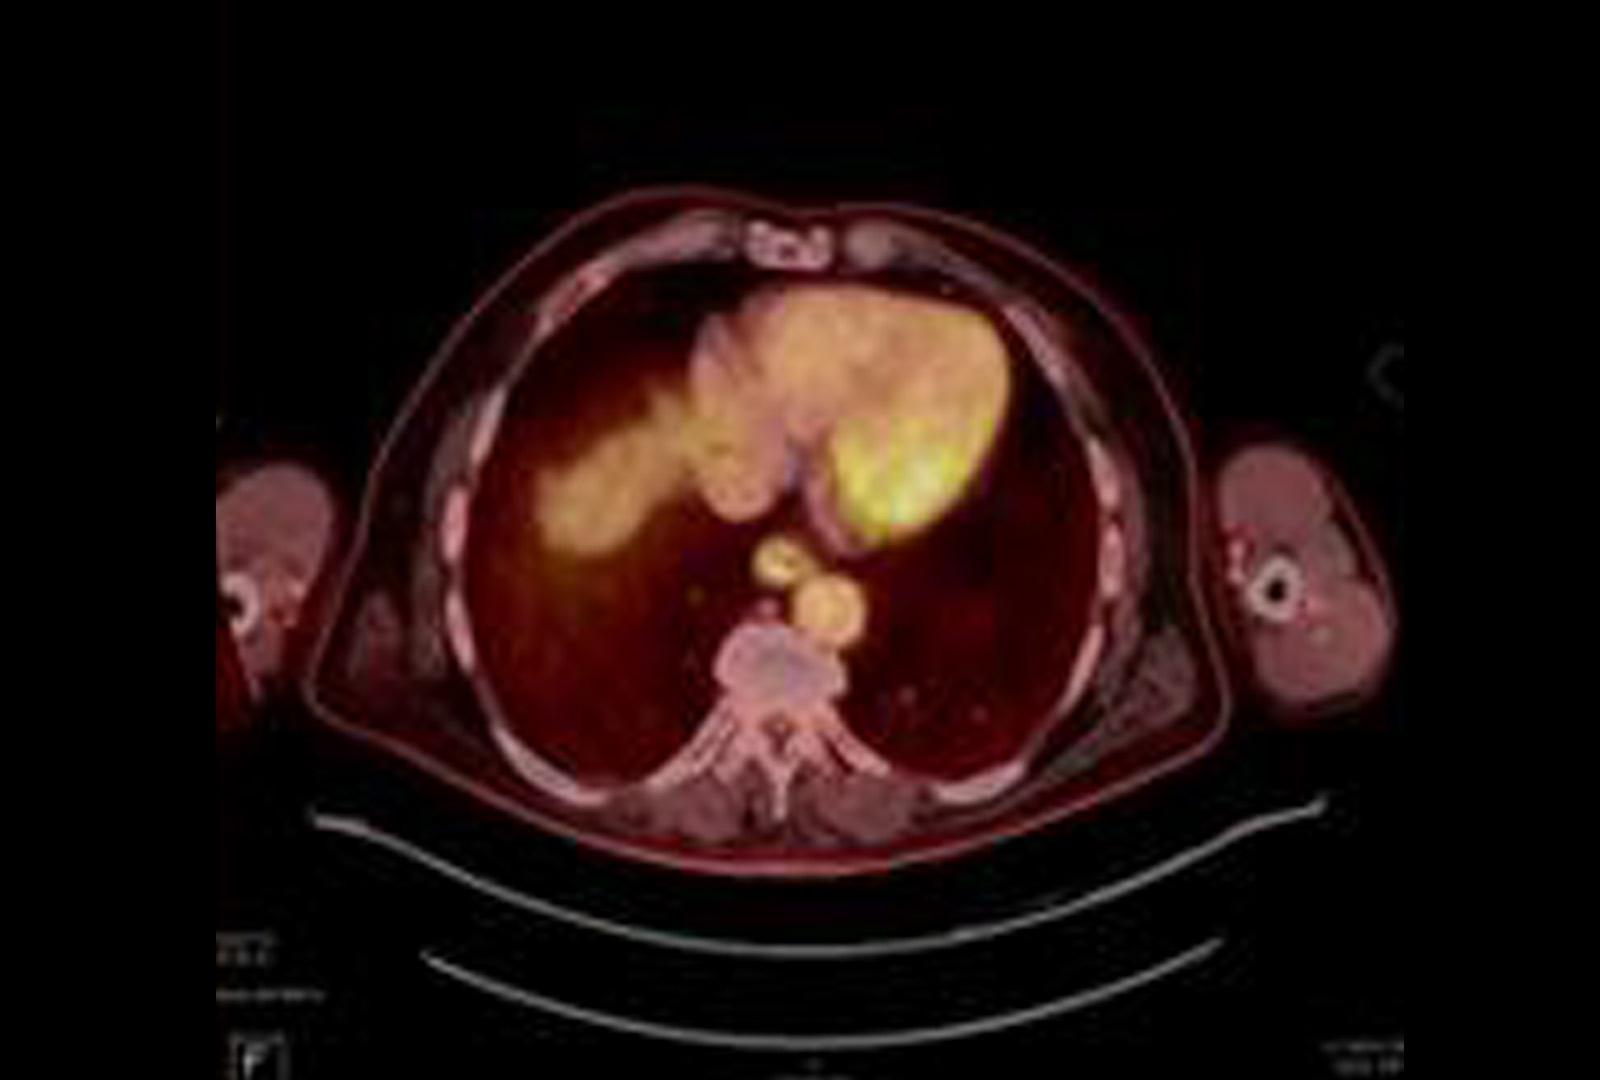

Further FDG Uptake in the Prostate

PET/CT demonstrating FDG uptake in the left basal to mid prostate correlating with elevated PSA. Source: NYU Langone Health